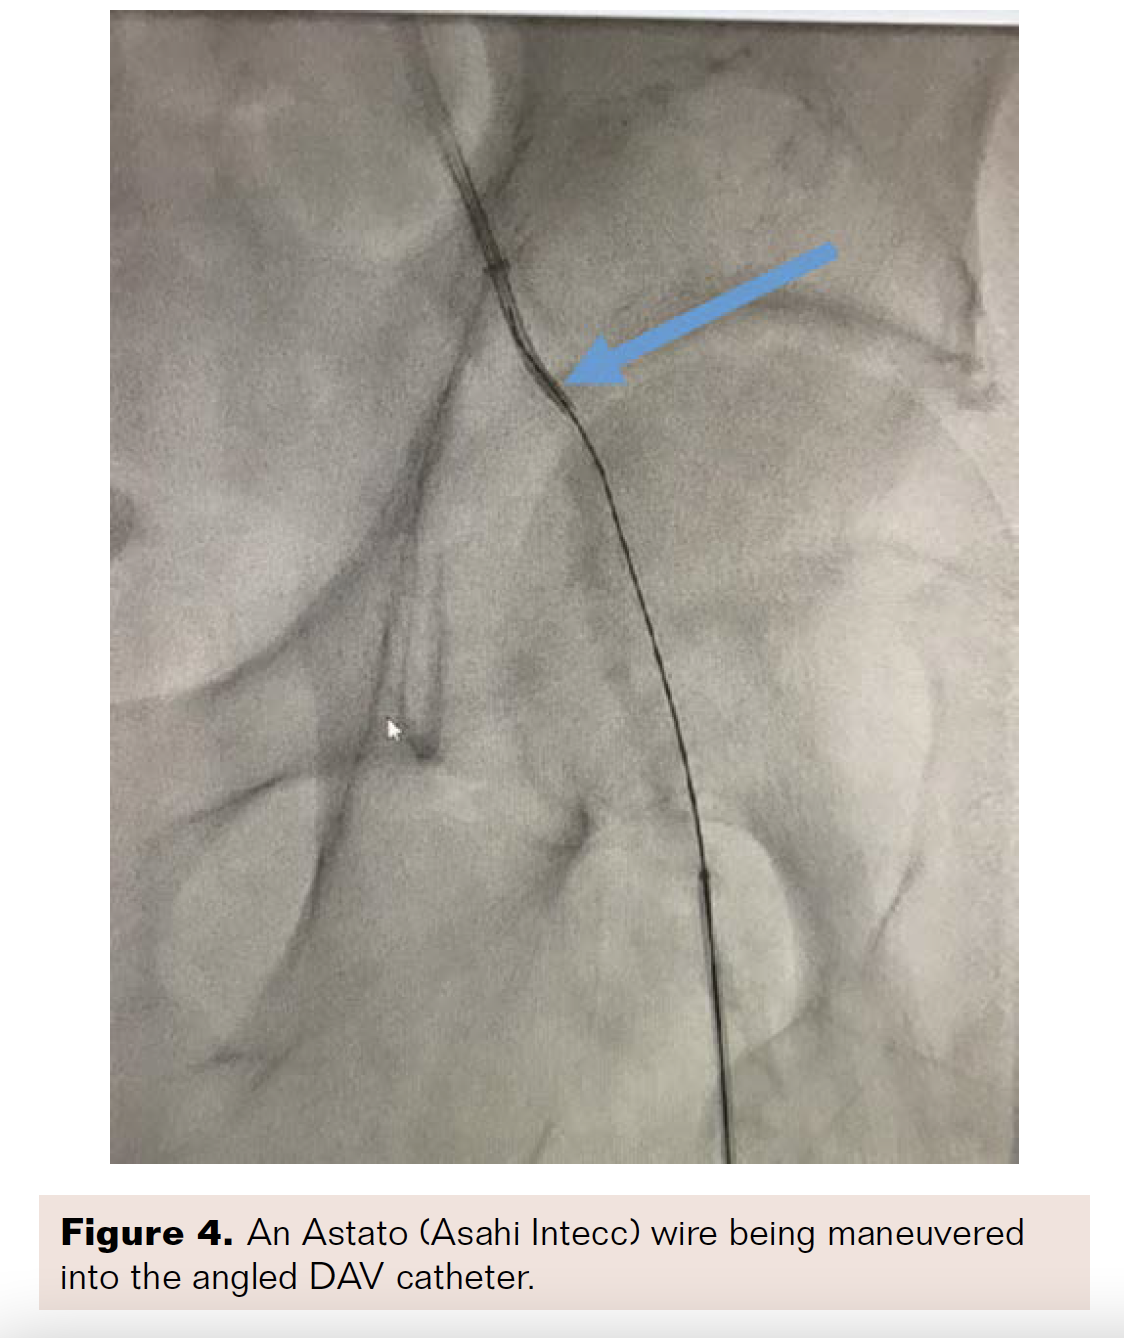

A 6 French (Fr), 45 cm sheath was placed at the level of the left common femoral artery (CFA) from a right contralateral, retrograde CFA access. An .018 inch × 90 cm NaviCross microcatheter (Terumo) and a .014-inch Victory wire (Boston Scientific) were used to cross the CTO of the SFA, but entered a subintimal plane. The patient was prepared for direct left SFA access. An 18-gauge needle, stiff Glidewire (Terumo), and NaviCross microcatheter were used to gain ipsilateral, retrograde access of the left SFA. The CTO was crossed successfully with the stiff Glidewire. The stiff glidewire was switched with a .014-inch, 40 g Astato wire (Asahi Intecc). A 5 Fr, angled DAV catheter (Cook Medical) was then inserted via the right CFA access, and the Astato wire was maneuvered into the angled DAV catheter (Figure 4). The Astato wire was externalized through the “flossing technique” out of the contralateral femoral access. Percutaneous transluminal angioplasty (PTA) of the SFA lesion with a 4 × 150 cm balloon (Cook Medical) was performed through the contralateral retrograde access and exchanged for a.035-inch Quick-Cross catheter (Philips). A Runthrough wire (Terumo) was placed alongside the Astato wire and was extended past the SFA access site.